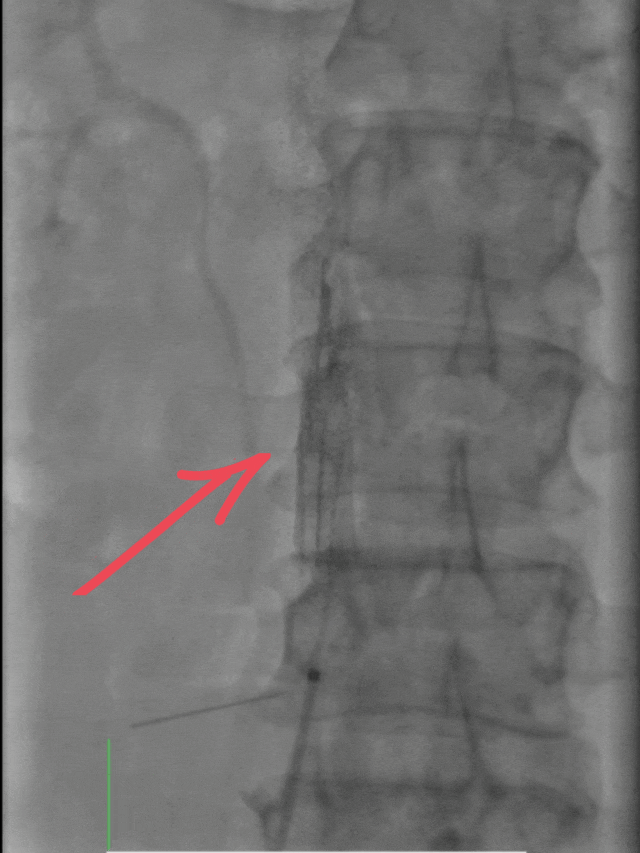

首先通过下肢静脉造影,清晰定位血栓位置与负荷;

随后置入下腔静脉滤器,如同在血管内筑起“防护网”,有效预防血栓脱落引发更严重的肺栓塞;